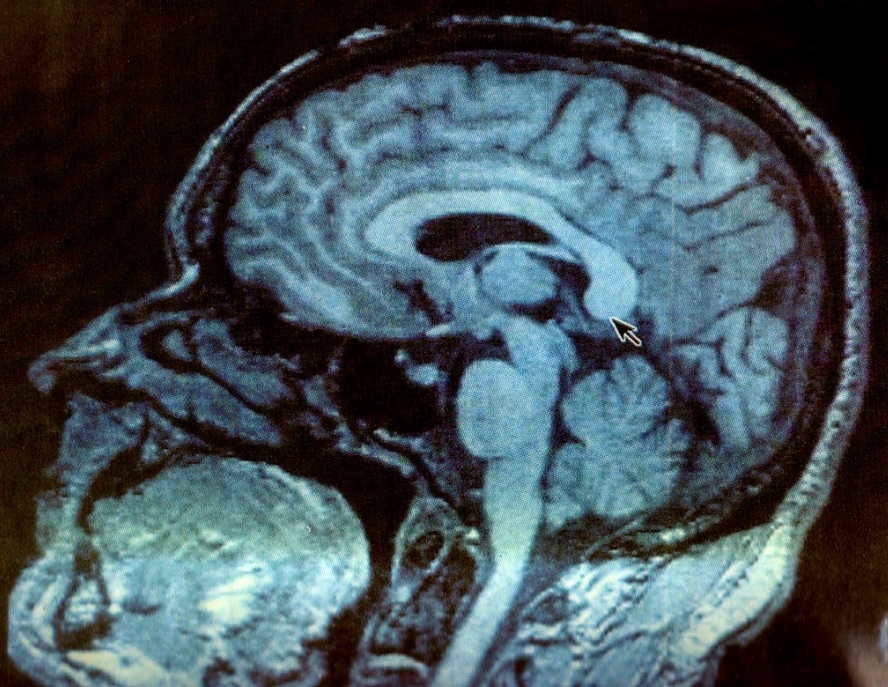

뇌동맥류 진단에는 일반적으로 일련의 의학적 검사가 포함됩니다. 의사는 CT 스캔 및 MRI와 같은 영상 기술을 사용하여 뇌의 혈관을 명확하게 파악할 수 있습니다.

이 과정은 치료 계획을 세우는 데 중요한 정보인 동맥류의 크기와 위치를 파악하는 데 도움이 됩니다.